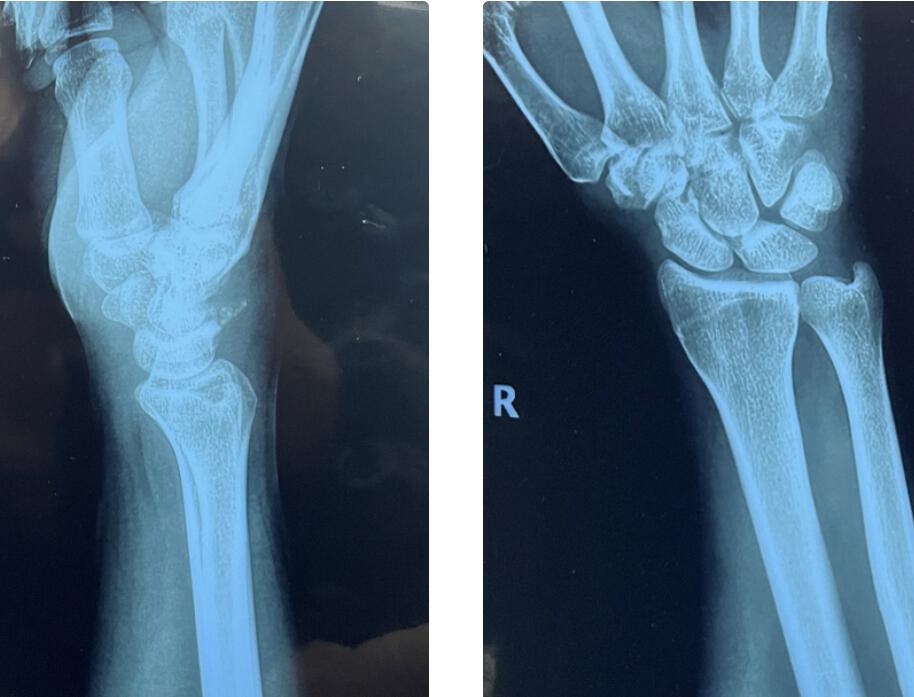

那是2022年的1月,Florian正骑行在广州的街道上,一辆突然窜出来的汽车将他撞倒在地,一阵刺骨的疼痛从撑地的手腕传来,他被紧急送往了医院。经X光及CT诊断,他的手腕部三角骨骨折。